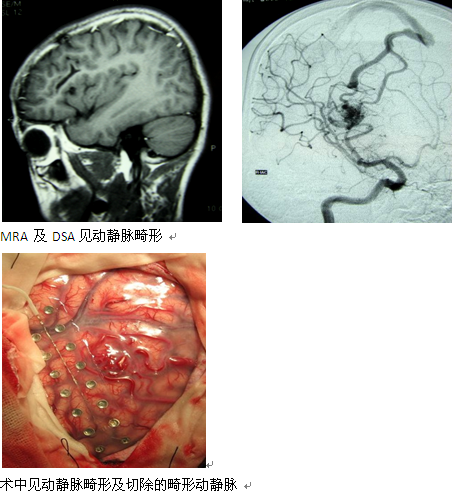

患儿郭xx,14岁,发作性意识不清8年,于外院诊断为癫痫,口服多种抗癫痫药物后不能控制,入院后查头部核磁及DSA,诊断为右额叶动静脉畸形 。

显微镜下开颅直接切除动静脉血管团的手术方法。术中切断畸形血管的供血动脉剥离畸形血管团,最后切断引流静脉。